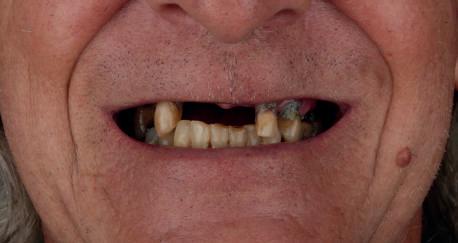

60 year old male patient visits the clinic with the desire to restore his oral health in a fully comprehensive manner.

Upon physical examination we found absence of teeth in both jaws and remaining teeth with recurrent caries, advanced periodontal disease and mobility; with a poor prognosis for function and aesthetics. We proceeded to take all the preparatory records such as: scans, photographs, x-rays, tomography and other diagnostic elements for the planning of rehabilitation by means of dental implants.

After 6 months the patient returns and records are taken for the final prosthesis. In this case the lower prosthesis is made of a titanium bar and a PMMA superstructure and the upper part is made of a titanium substructure and a zirconia structure.